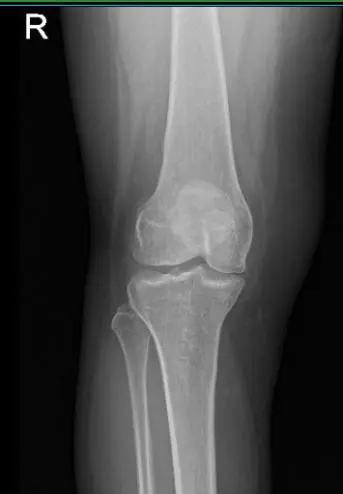

Patient is a 49 year-old female, in our office with complaints of LS spine and right knee pain. He experienced the pain about 8 months ago. The patient remembers his injury in a motor vehicle accident. The pain is extremely severe in intensity. The patient describes the pain as sharp, dull, stabbing.

She presented her old X-ray done 8 months ago and suspected to have a medial meniscus tear of right knee. Suggested to take another X-ray/MRI to see the reason behind the pain. This time the patient agreed to take Cortisone injection to ease the pain somehow.

MRI of right knee

Patient returned and presented her MRI- found Tri compartment degenerative chest, with cartilage loss most pronounced in the patellofemoral compartment.

Complex tear involving the anterior horn lateral meniscus with a horizontal component extending into the body lateral meniscus with small joint effusion.